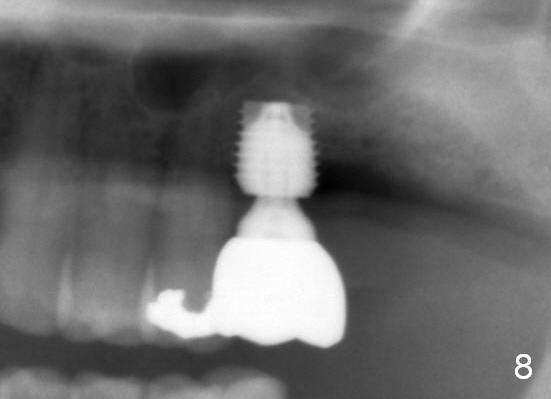

When the patient returns for impression 6.5 months postop, the provisional has dislodged because of the short abutment (Fig.7 A (6.5x4(2) mm). A longer one is placed (6.5x5(3) mm). When he returns for crown cementation 8.5 months postop, the provisional is retentive. The distal implant plateau is still exposed. Post-cementation panoramus shows that the distal 3 threads are not covered by the bone and that the crown/implant ratio is 5:3 (Fig.8). Implants are recommended at #3 and 30 (Fig.9). There is a distinct layer of bone apical to the implant at #14 22 months post cementation (Fig.10 *). In spite of exposure of 2-3 threads distally, there is no sign of peri-implantitis. It appears that the implant is subgingival (Fig.11 (BW) white dashed line: gingival margin). The implant remains infection free 3 years 10 months post cementation (Fig.12) due to the thick gingiva and good oral hygiene.